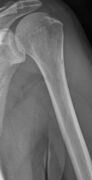

The diagnostic examination of a person with suspected multiple myeloma typically includes a skeletal survey. This is a series of X-rays of the skull, axial skeleton, and proximal long bones. Myeloma activity sometimes appears as "lytic lesions" (with local disappearance of normal bone due to resorption) or as "punched-out lesions" on the skull X-ray ("raindrop skull"). Lesions may also be sclerotic, which is seen as radiodense.[70] Overall, the radiodensity of myeloma is between −30 and 120 Hounsfield units (HU).[71] Magnetic resonance imaging is more sensitive than simple X-rays in the detection of lytic lesions, and may supersede a skeletal survey, especially when vertebral disease is suspected. Occasionally, a CT scan is performed to measure the size of soft-tissue plasmacytomas. Nuclear Medicine Bone scans are typically not of any additional value in the workup of people with myeloma (no new bone formation; lytic lesions not well visualized on nuclear bone scan).

X-ray of the forearm, with lytic lesions

Skull X-ray showing multiple lucencies due to multiple myeloma

Multiple myeloma in the upper arm

Humerus with multiple myeloma lesions

Same humerus before, with just subtle lesions